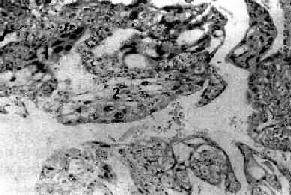

图13-13 绒毛膜癌 癌组织没有间质,癌巢由于两种细胞组成:1.合体细胞样细胞;2.细胞滋养层细胞样细胞 绒癌易侵入血管,故主要为血行转移,最多见转移至肺,其次为阴道、脑、肝、脾、肾、肠等。自应用化疗后,绒癌的死亡率已显著下降。